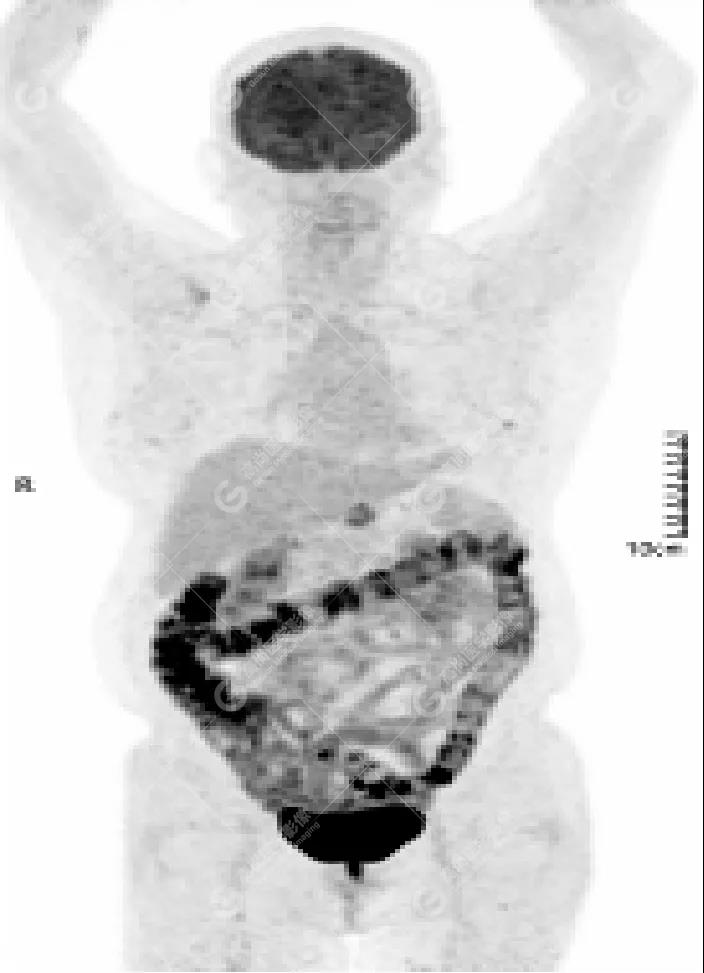

女性 67歲 因背痛查體,糖尿病11年。腫瘤標(biāo)記物:CEA 6.4↑,AFP、CA125、CA199正常。外院MR檢查:胸11椎體-附件左份異常信號(hào),增強(qiáng)環(huán)狀強(qiáng)化,骨原發(fā)?轉(zhuǎn)移?感染?PET/CT影像圖

胸椎溶骨性骨質(zhì)破壞,F(xiàn)DG環(huán)狀代謝增高,SUVmax為4.0。

左側(cè)乳腺一軟組織結(jié)節(jié),F(xiàn)DG代謝增高,SUVmax為2.6。

最終診斷:左側(cè)乳腺癌伴胸椎單發(fā)骨轉(zhuǎn)移。